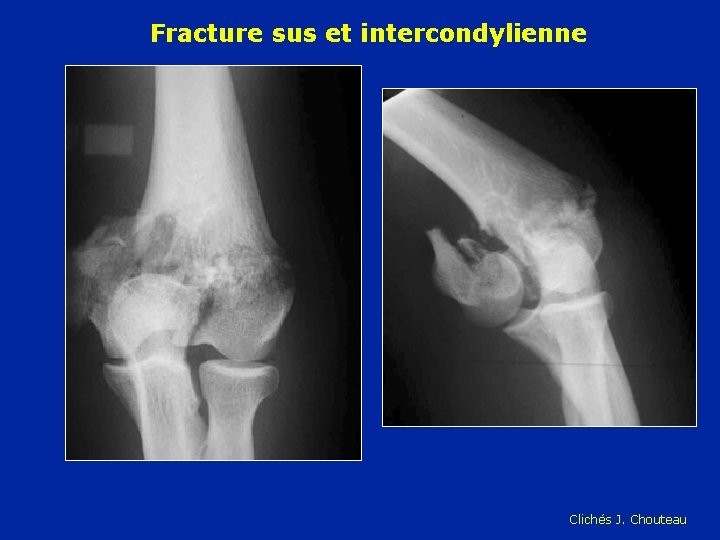

Fracture sus et intercondylienne Clichés J. Chouteau